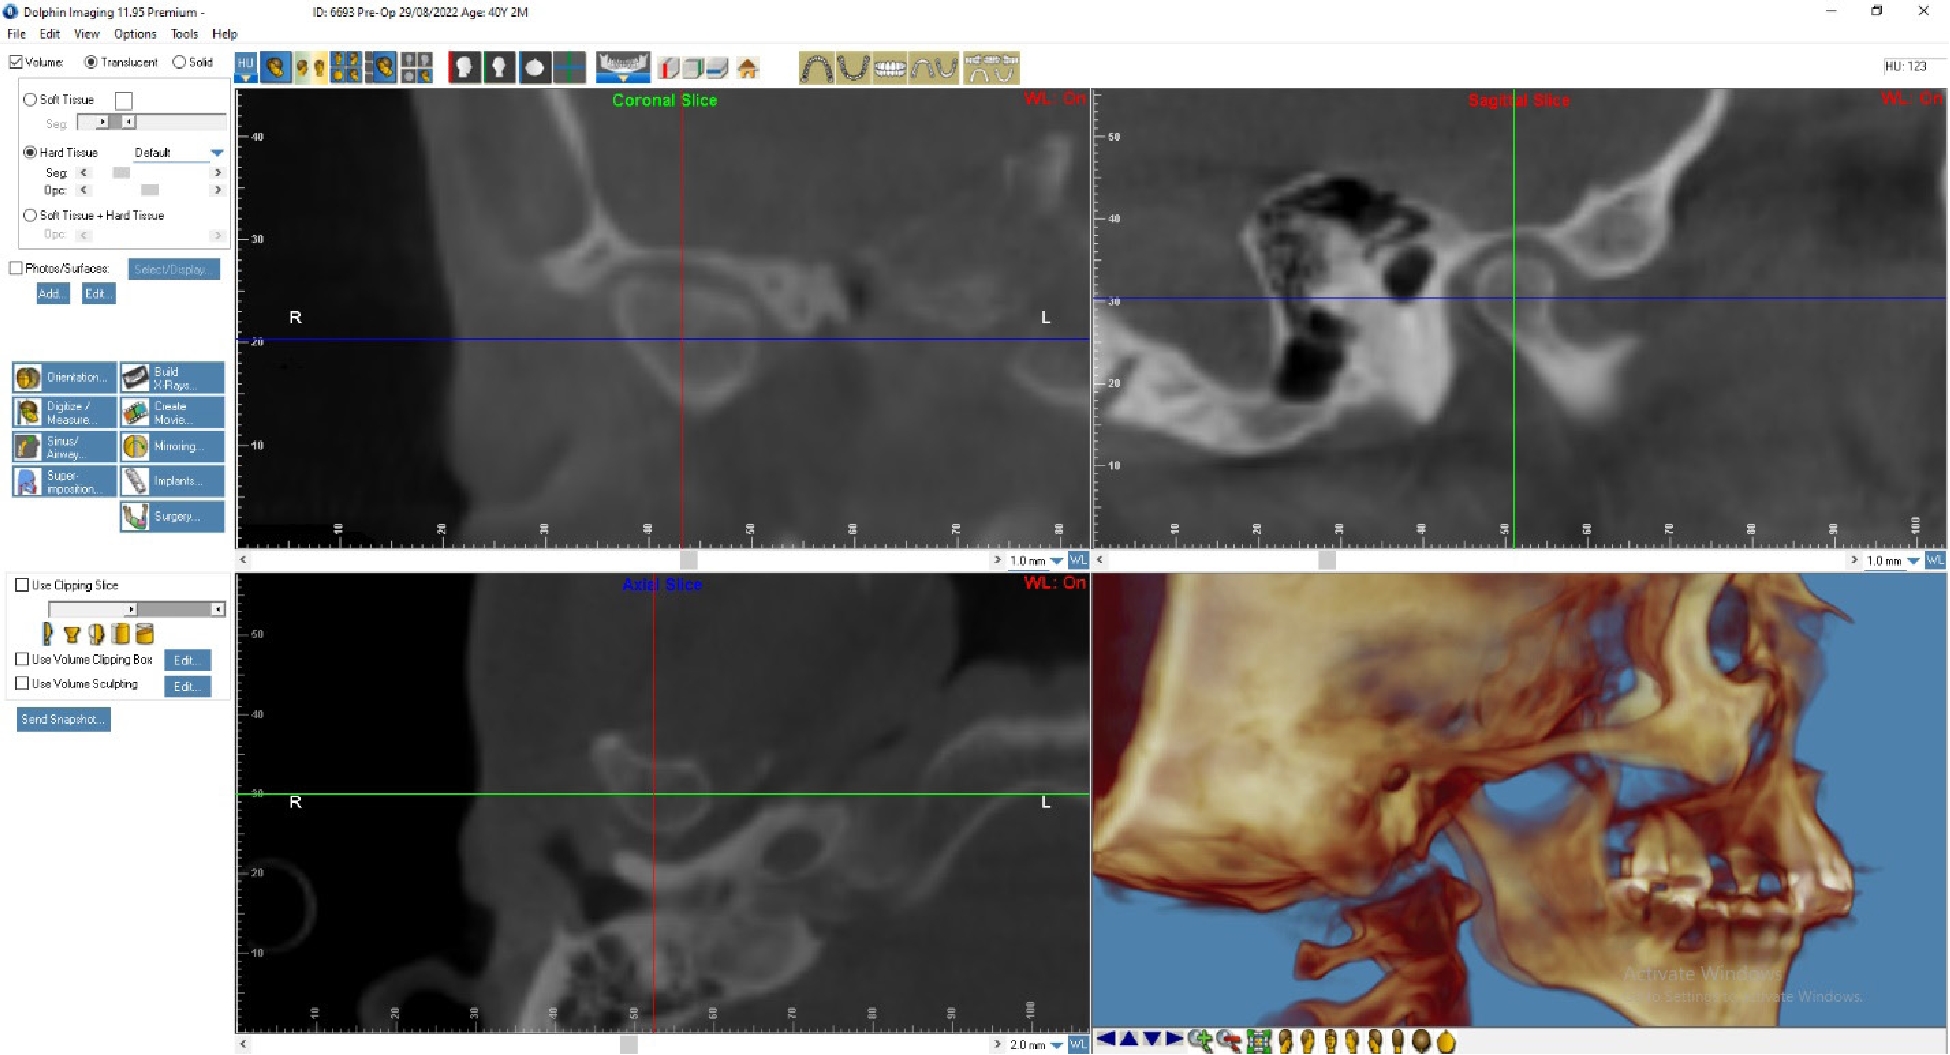

Лечение: Пациенту Д. была выполнена окклюзиограмма, на основании которой были устранены супраконтакты методом избирательного пришлифовывания зубов. Также было выполнено лечение сплинт-терапией для восстановления работы височно-челюстного сустава. Фиксирована брекет-система на зубы нижней челюсти (рис. 3, 4).

По данным МРТ ВНЧС спустя 2 года после начала лечения отмечается устранение вентро-латеральной дислокации суставного диска в положении привычной окклюзии. Также устранен синовит, увеличился объем движения в суставе (рис. 5). Как видно из рис. 4 и 5, по данным КТ ВНЧС спустя 2 года после начала лечения отмечается ремоделирование головки нижней челюсти. Клинически увеличилось открывание рта до 38 мм.

Рис. 3. Пациент Д., 38 лет. Начало лечения

Рис. 5. Пациент Д., 40 лет. КТ ВНЧС спустя 2 года после начала лечения